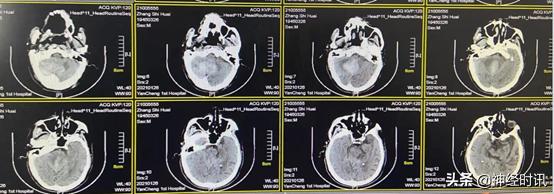

2月1日(脑血疏用药10 d后)复查CT,显示患者小脑血肿进一步淡化吸收,血肿量约15 ml,脑干及环池显示完全,效果明显,继续服用脑血疏口服液

2月8日(脑血疏用药两周半后)复查CT,显示患者小脑血肿基本淡化吸收,量约10 ml,水肿达到高峰,但并未对脑干造成压迫,继续口服脑血疏口服液